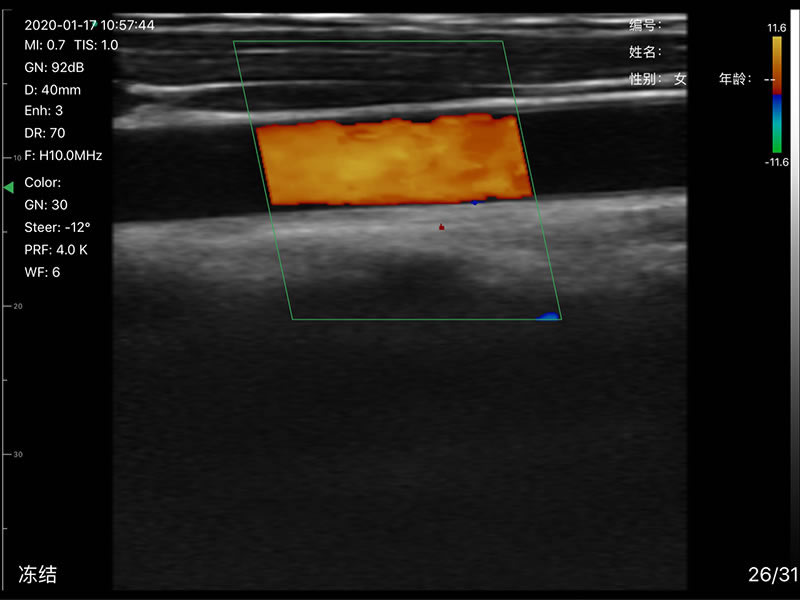

• 显示模式:B、B/M、Color、PW、PDI

• 探头频率:相控阵2.2/3.6MHz,线阵7.5/10 MHz